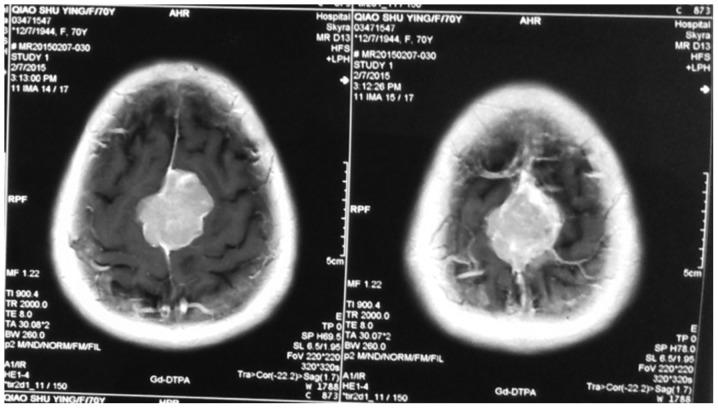

Imaging characteristics and surgical treatment of invasive meningioma.

In order to provide an effective way to prevent or substantially delay the recurrence of invasive meningioma, and improve the curative effect of surgical treatment, we collected and analyzed the clinical manifestations, pathological features, preoperative imaging characteristics as well the data obtained during the surgical treatment of invasive meningioma. From February 2014 to February 2016, 59 patients with invasive meningioma were enrolled in this study. Invasive meningioma was confirmed in all patients by operation. Information about clinical manifestations, pathological features, preoperative imaging and surgical treatment were collected and analyzed. After surgery, pathological specimens were collected, and cases were confirmed as invasive meningioma by pathological examination. The course of disease ranged from 15 days to 7 years (average, 13.2 months). We used World Health Organization (WHO) criteria for classification of meningioma in the nervous system tumors as our reference. Symptoms were as follows: Intracranial hypertension (29 cases), cranial nerve dysfunction (10 cases), epilepsy (11 cases) and other symptoms (9 cases). We had 56 cases of WHO grade I; 6 cases of WHO grade II and 7 cases of WHO grade III. Surgical removal was: Simpson grade I (56 cases), Simpson grade II (2 cases), Simpson grade III and above (56 cases). We used before surgery imaging data to formulate our surgical plan. In general, during surgeries we did not proceed to complete resection, because in the majority of cases, some key structures were invaded and meningioma was very deep and any attempt for total resection could easily lead to significant damage to these structures.